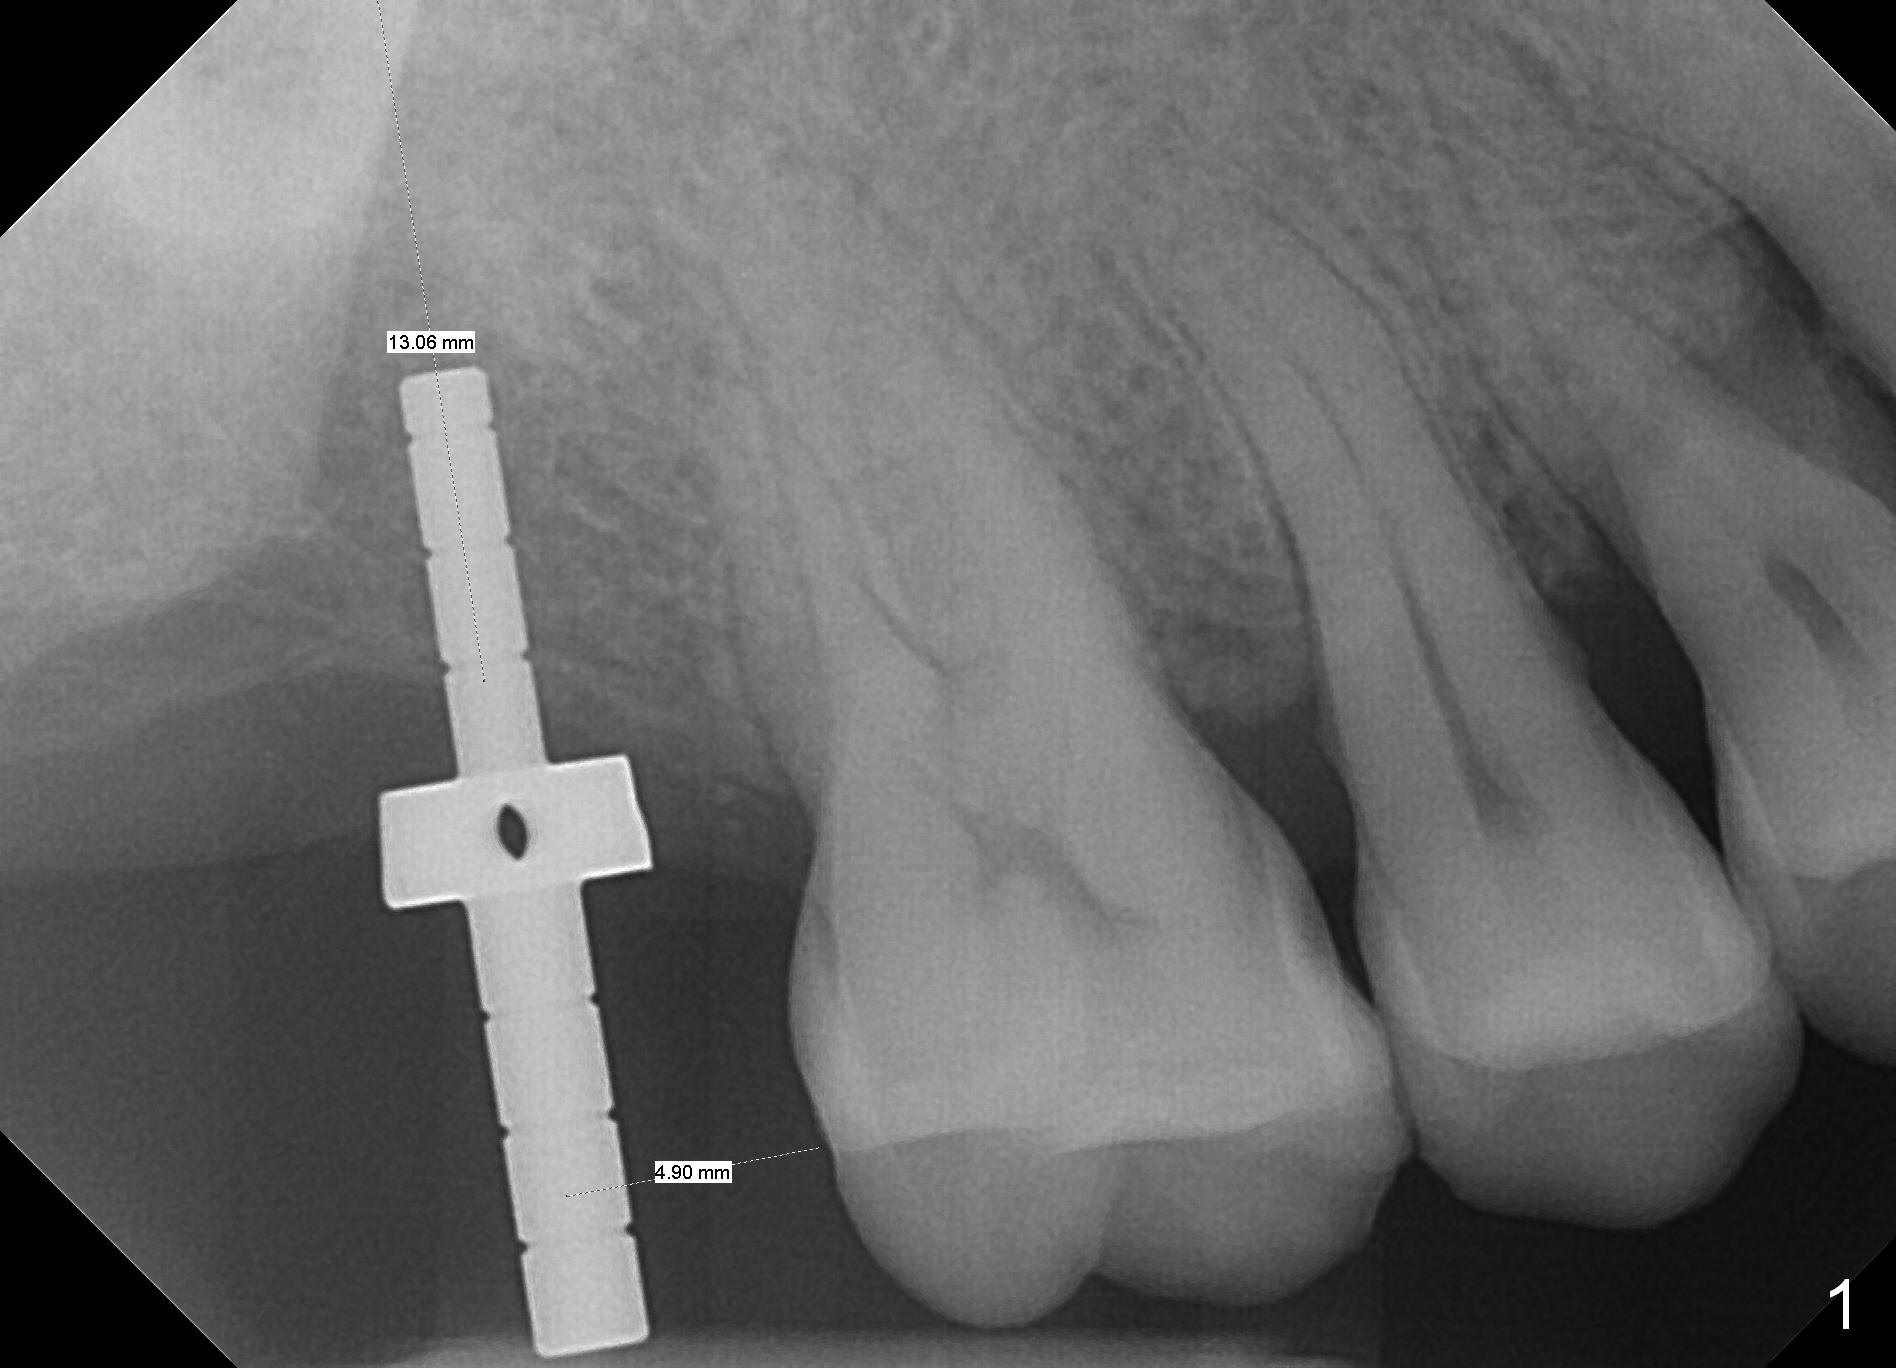

The edentulous ridge at the site of #2 is wide. Magic split is used to gain access, test bone density and start osteotomy for 9 mm (gingival level). A 1.6 mm drill is used to extend the osteotomy for depth of 13 mm. The osteotomy position and trajectory is confirmed with a parallel pin (Fig.1), which is ideal. The remaining osteotomy is finished with Magic Expanders from 3 to 4.3 mm for 15 mm. The trajectory is confirmed again with insertion of a 4.5x11 mm dummy implant at the depth of 15 mm (Fig.2). When a definitive IBS implant (5x13 mm) is placed with insertion torque >45 Ncm, the distal coronal end is not subcrestal (Fig.3-5). As the implant is placed deeper, it started to lose primary stability. When a pair abutment is placed, it keeps turning. Finally a healing abutment (6x3 mm) is placed unstable. In brief, taking several X-ray films help control osteotomy and implant position and trajectory. The implant is unstable 7 months postop (Fig.6). With local anesthesia, the implant is placed deeper by 1 mm with apparent increase in torque and a 6x4 healing abutment placed. The implant is stable 11 months postop. With 5.5x4(4) mm abutment placed, impression is taken. PA and BW will be taken after cementation of the crown. There is no bone loss 9 months post cementation (Fig.7). Return to Upper Molar Immediate Implant, 18-20, 29,30 Xin Wei, DDS, PhD, MS 1st edition 01/09/2017, last revision 08/15/2021